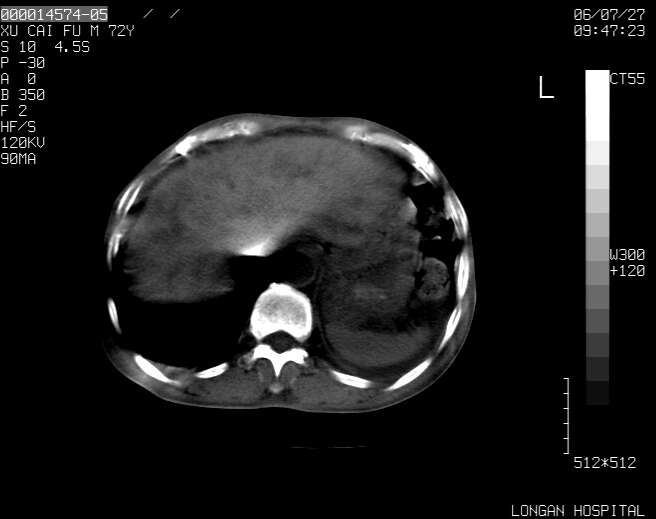

以下是引用winter在2006-7-30 20:14:00的发言:[br]1、考虑胆囊癌伴胆道侵犯并高位胆道梗阻、肝内多发转移、腹膜后淋巴结转移。[br]2、右肾轻度积水。[br]3、老人家72岁了胰腺头体尾部均较饱满,不过未见密度异常及其他异常征象。[br]4、腹水。

以下是引用jiajie在2006-7-31 7:10:00的发言:[br]考虑肝转移瘤,腹膜后淋巴结增大。[br]胃癌不能除外,建议胃镜检查。